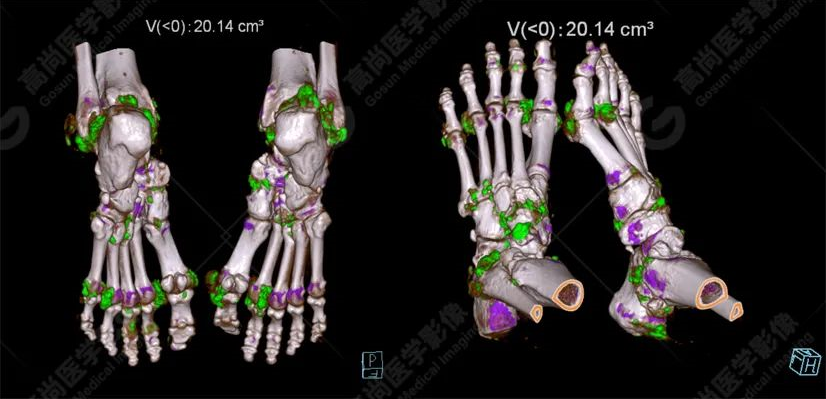

患者為60歲男性,既往確診痛風(fēng)性關(guān)節(jié)炎,雙手及雙足多發(fā)軟組織腫塊結(jié)節(jié),疼痛不適,活動受限,尿酸明顯增高,多次檢測尿酸超過500umol/L。

雙足VR圖像

雙手VR圖像